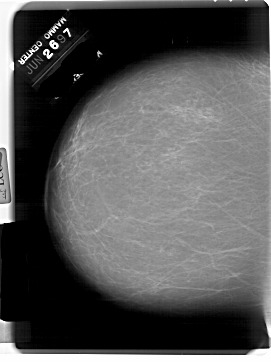

A_1796_1.RIGHT_MLO

RIGHT_MLO LINES 6871 PIXELS_PER_LINE 4336 BITS_PER_PIXEL 12 RESOLUTION 43.5 OVERLAY